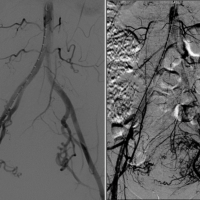

During UFE, a catheter is inserted through a blood vessel in the groin or arm and guided by X-ray images to the blood vessels that feed the fibroids of the uterus. Tiny particles are then injected to stop blood flow to the fibroids. Once blood flow to the fibroids is blocked, patients return home while the fibroids shrink gradually over the next weeks and months.

During the procedure a tiny catheter is precisely guided from an artery in the wrist or inguinal region until it reaches the superior rectal artery branches of the inferior mesenteric artery, which supplies blood to the hemorrhoids. Once the catheter is in position, embolic agents, such as small particles or coils, are injected into the artery to block the blood flow to the hemorrhoids. By blocking the blood supply to the hemorrhoidal tissue, the hemorrhoids shrink and eventually resolve. The procedure is typically performed under moderate sedation with the patient asleep. This procedure is generally considered a safe and effective treatment option for symptomatic hemorrhoids, offering a shorter recovery time and potentially fewer complications compared to traditional surgery.